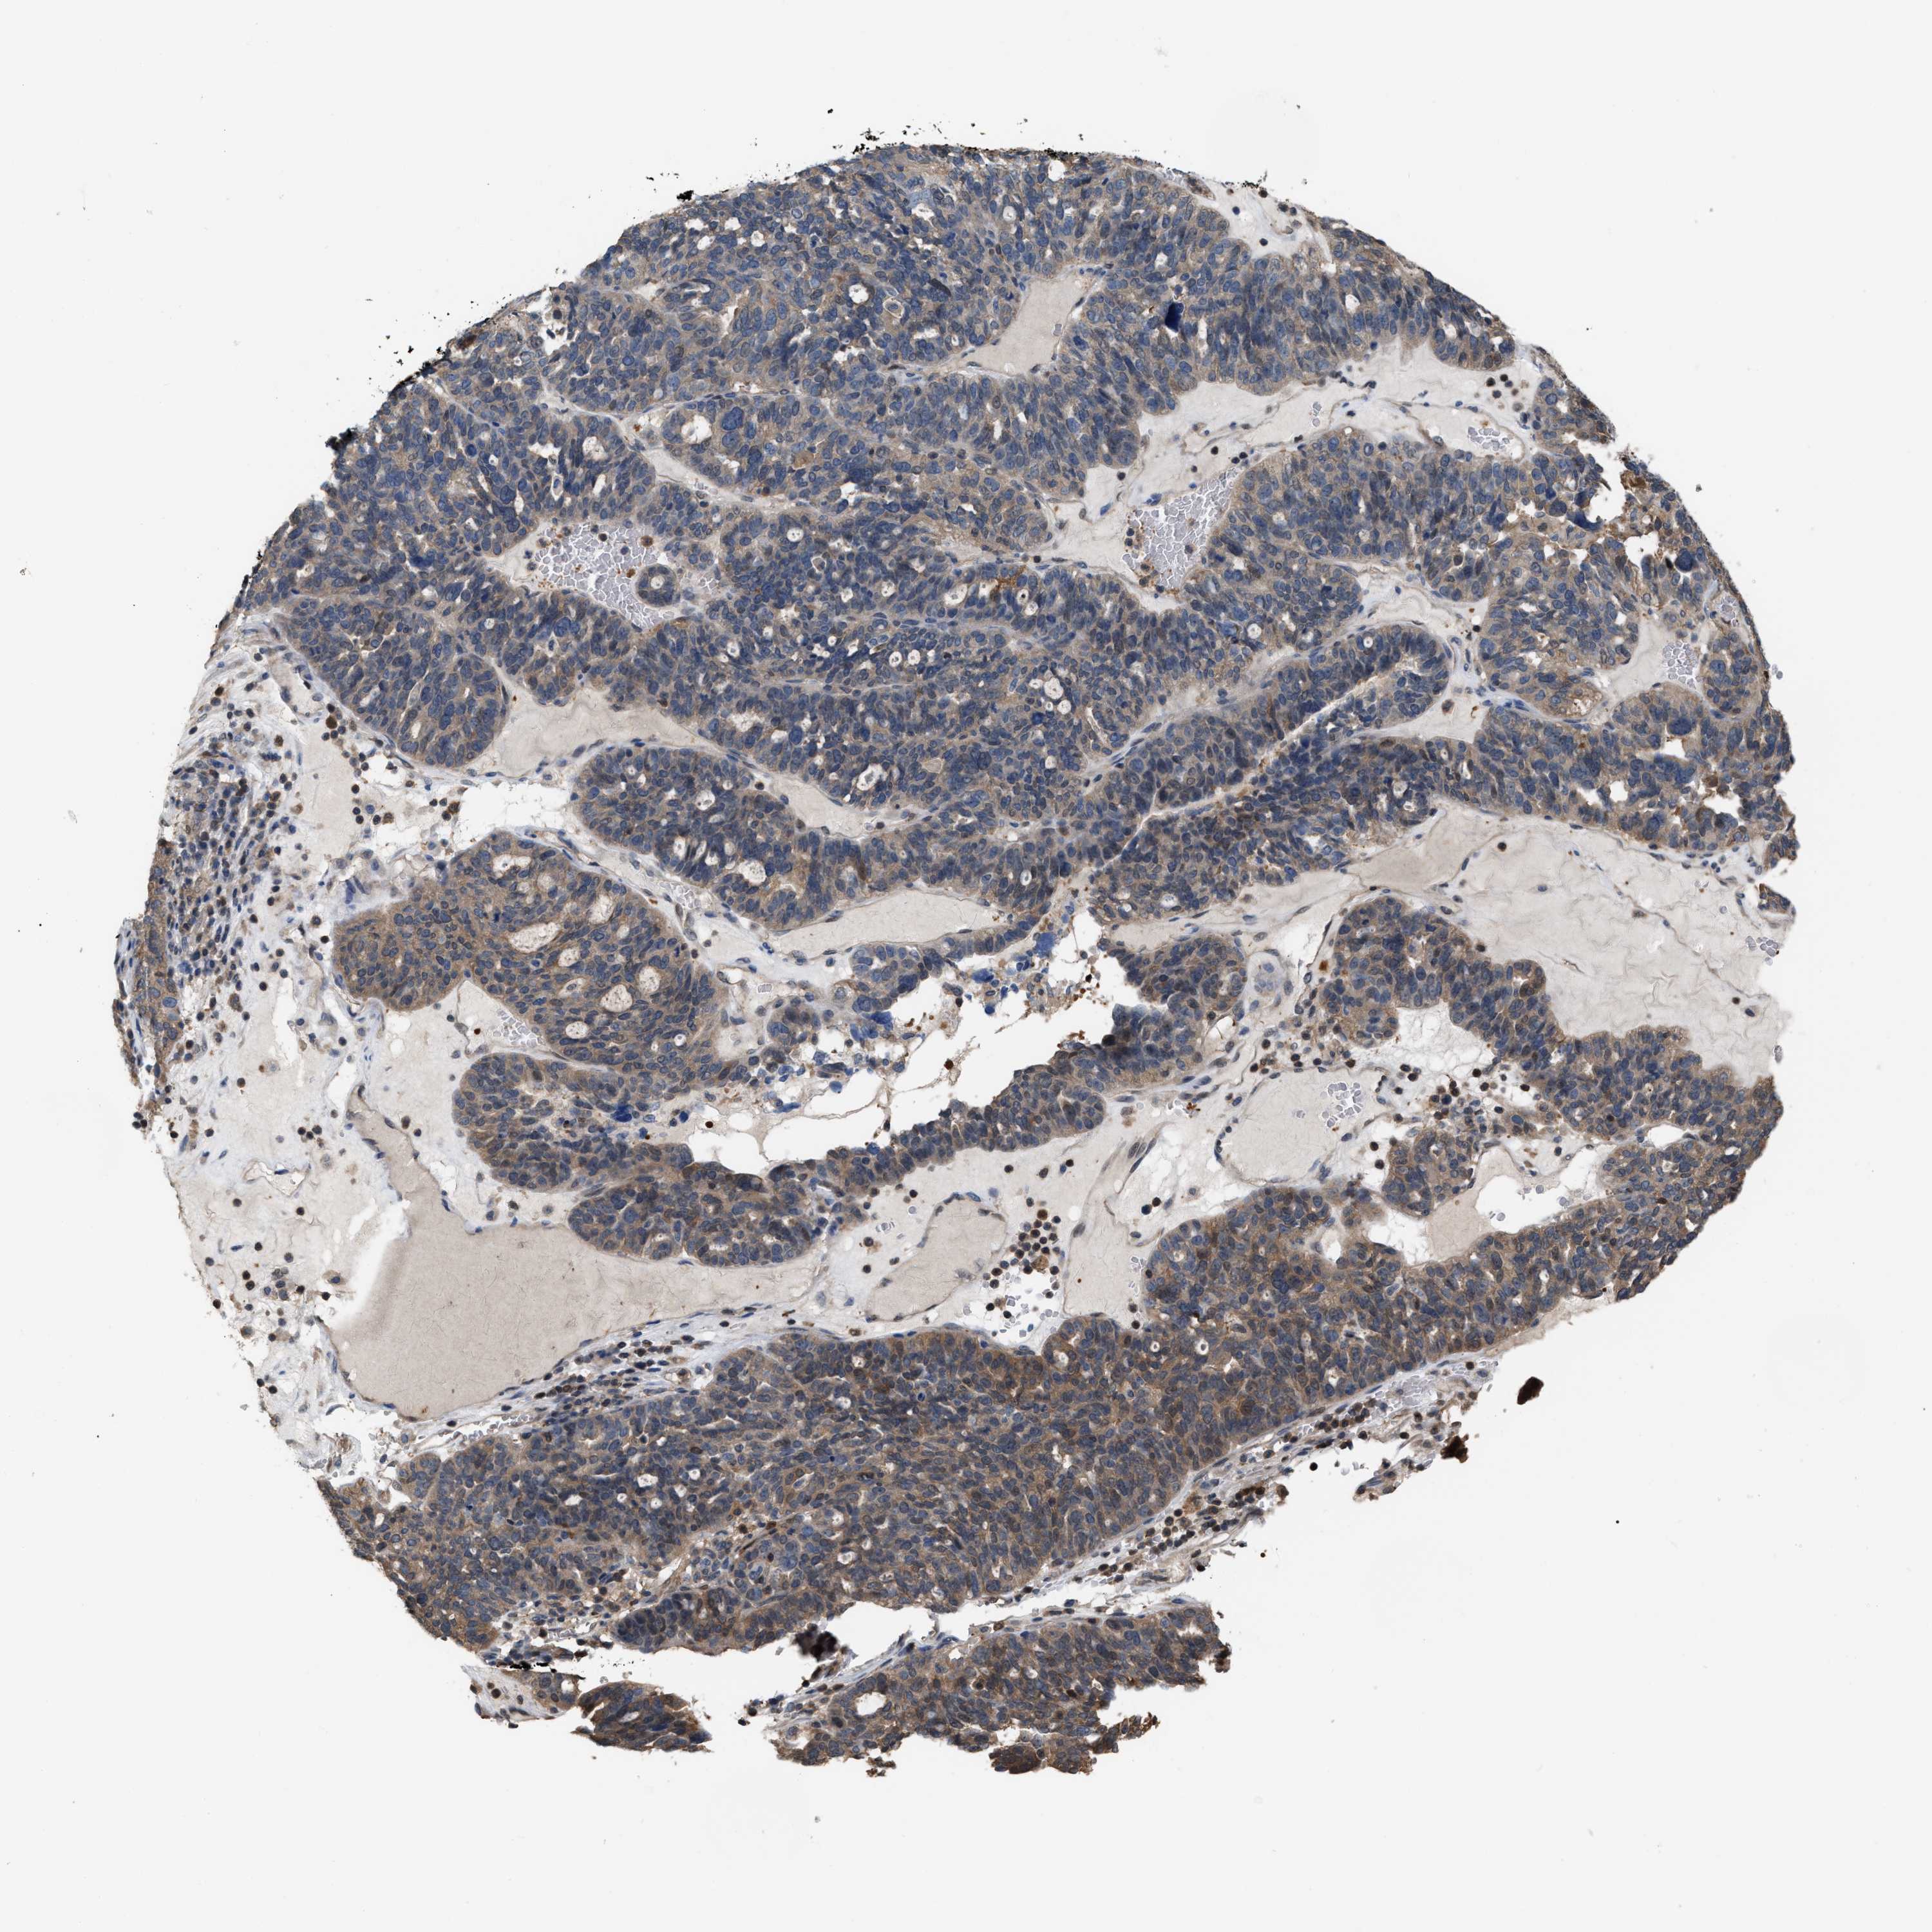

OVARIAN CANCER - Protein expressioni

A mouse-over function shows sample information and annotation data. Click on an image to view it in a full screen mode. Samples can be filtered based on level of antibody staining by selecting one or several of the following categories: high, medium, low and not detected. The assay and annotation is described here.

Note that samples used for immunohistochemistry by the Human Protein Atlas do not correspond to samples in the TCGA dataset.

Antibody stainingi

Antibody staining in the annotated cell types in the current human tissue is reported as not detected, low, medium, or high, based on conventional immunohistochemistry profiling in selected tissues. This score is based on the combination of the staining intensity and fraction of stained cells.

Each image is clickable and will lead to virtual microscopy that enables deeper exploration of all samples and also displays staining intensity scores, fraction scores and subcellular localization as well as patient and tissue information for each sample.

Antibody HPA019735

Staining

High

Medium

Low

Not detected

Intensity

Strong

Moderate

Weak

Negative

Quantity

>75%

75%-25%

<25%

None

Location

Nuclear

Cytoplasmic/membranous

Cytoplasmic/membranous,nuclear

Cystadenocarcinoma, serous, NOS

Carcinoma, endometroid

Cystadenocarcinoma, mucinous, NOS

Carcinoma, NOS